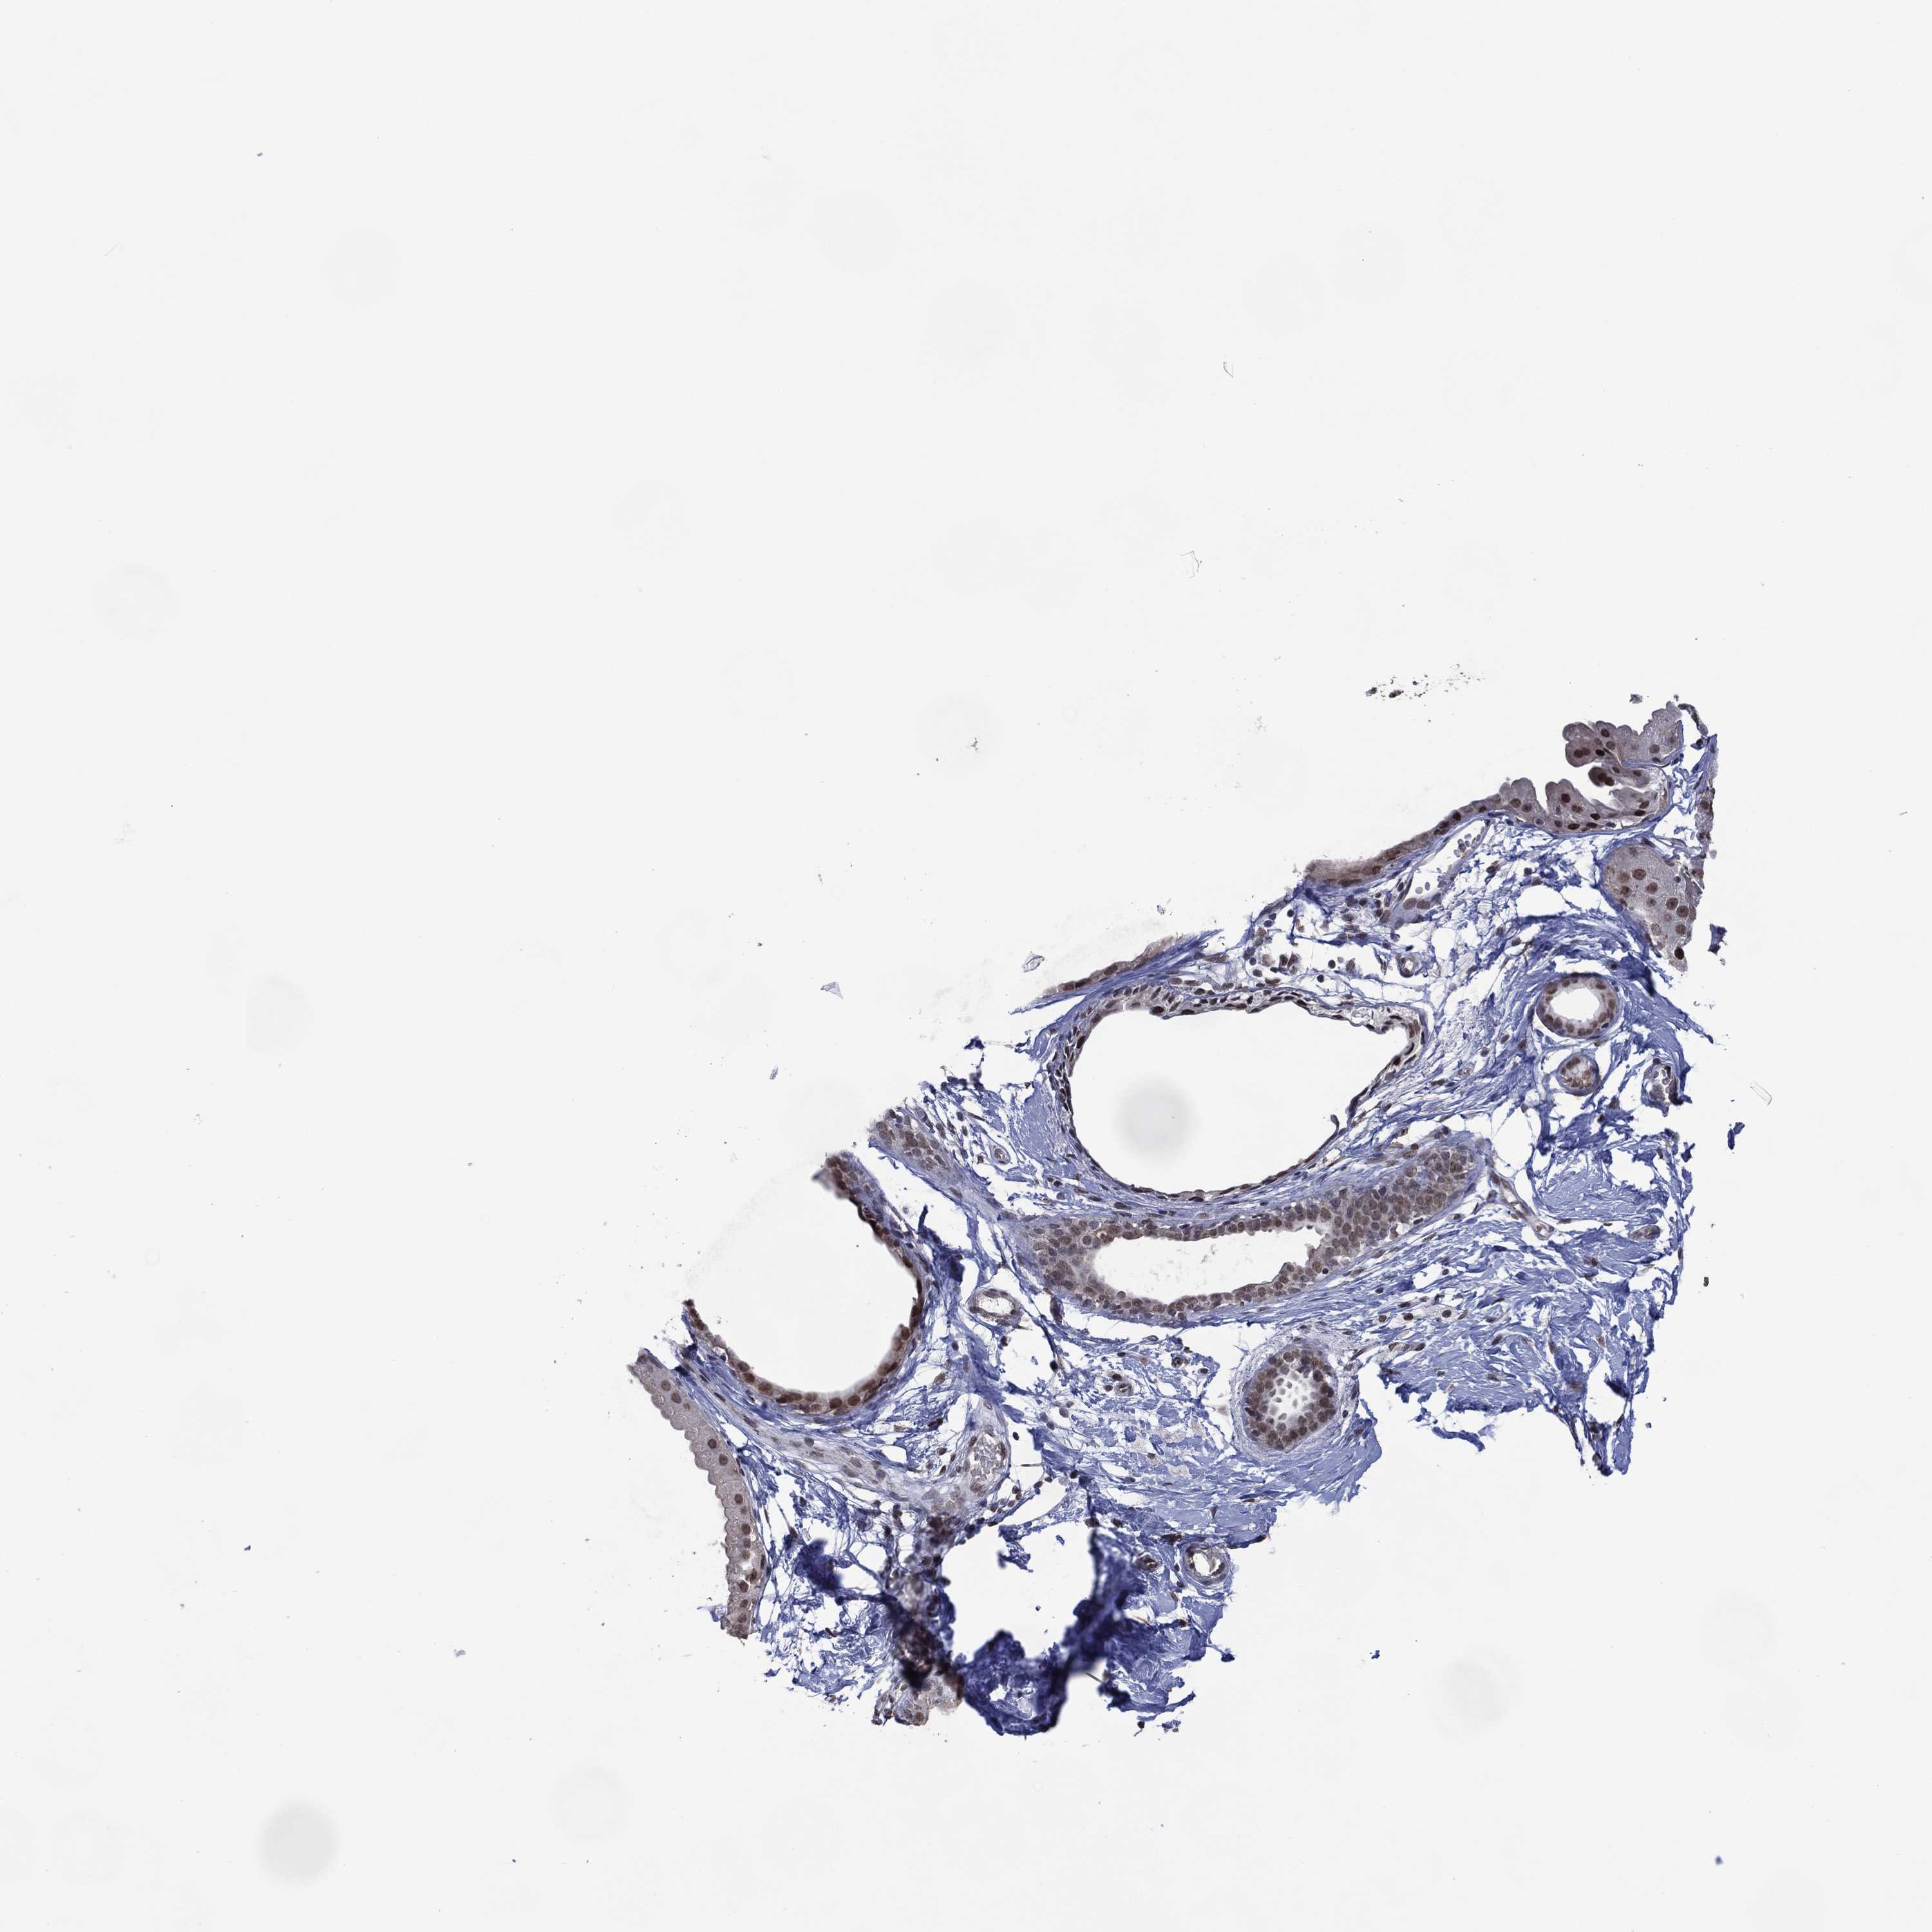

BREAST - Antibody stainingi

Antibody staining in the annotated cell types in the current human tissue is reported as not detected, low, medium, or high, based on conventional immunohistochemistry profiling in selected tissues. This score is based on the combination of the staining intensity and fraction of stained cells.

Each image is clickable and will lead to virtual microscopy that enables deeper exploration of all samples and also displays staining intensity scores, fraction scores and subcellular localization as well as patient and tissue information for each sample.

Antibody HPA074729

Adipocytes Not detected

Glandular cells Low

Myoepithelial cells Not detected